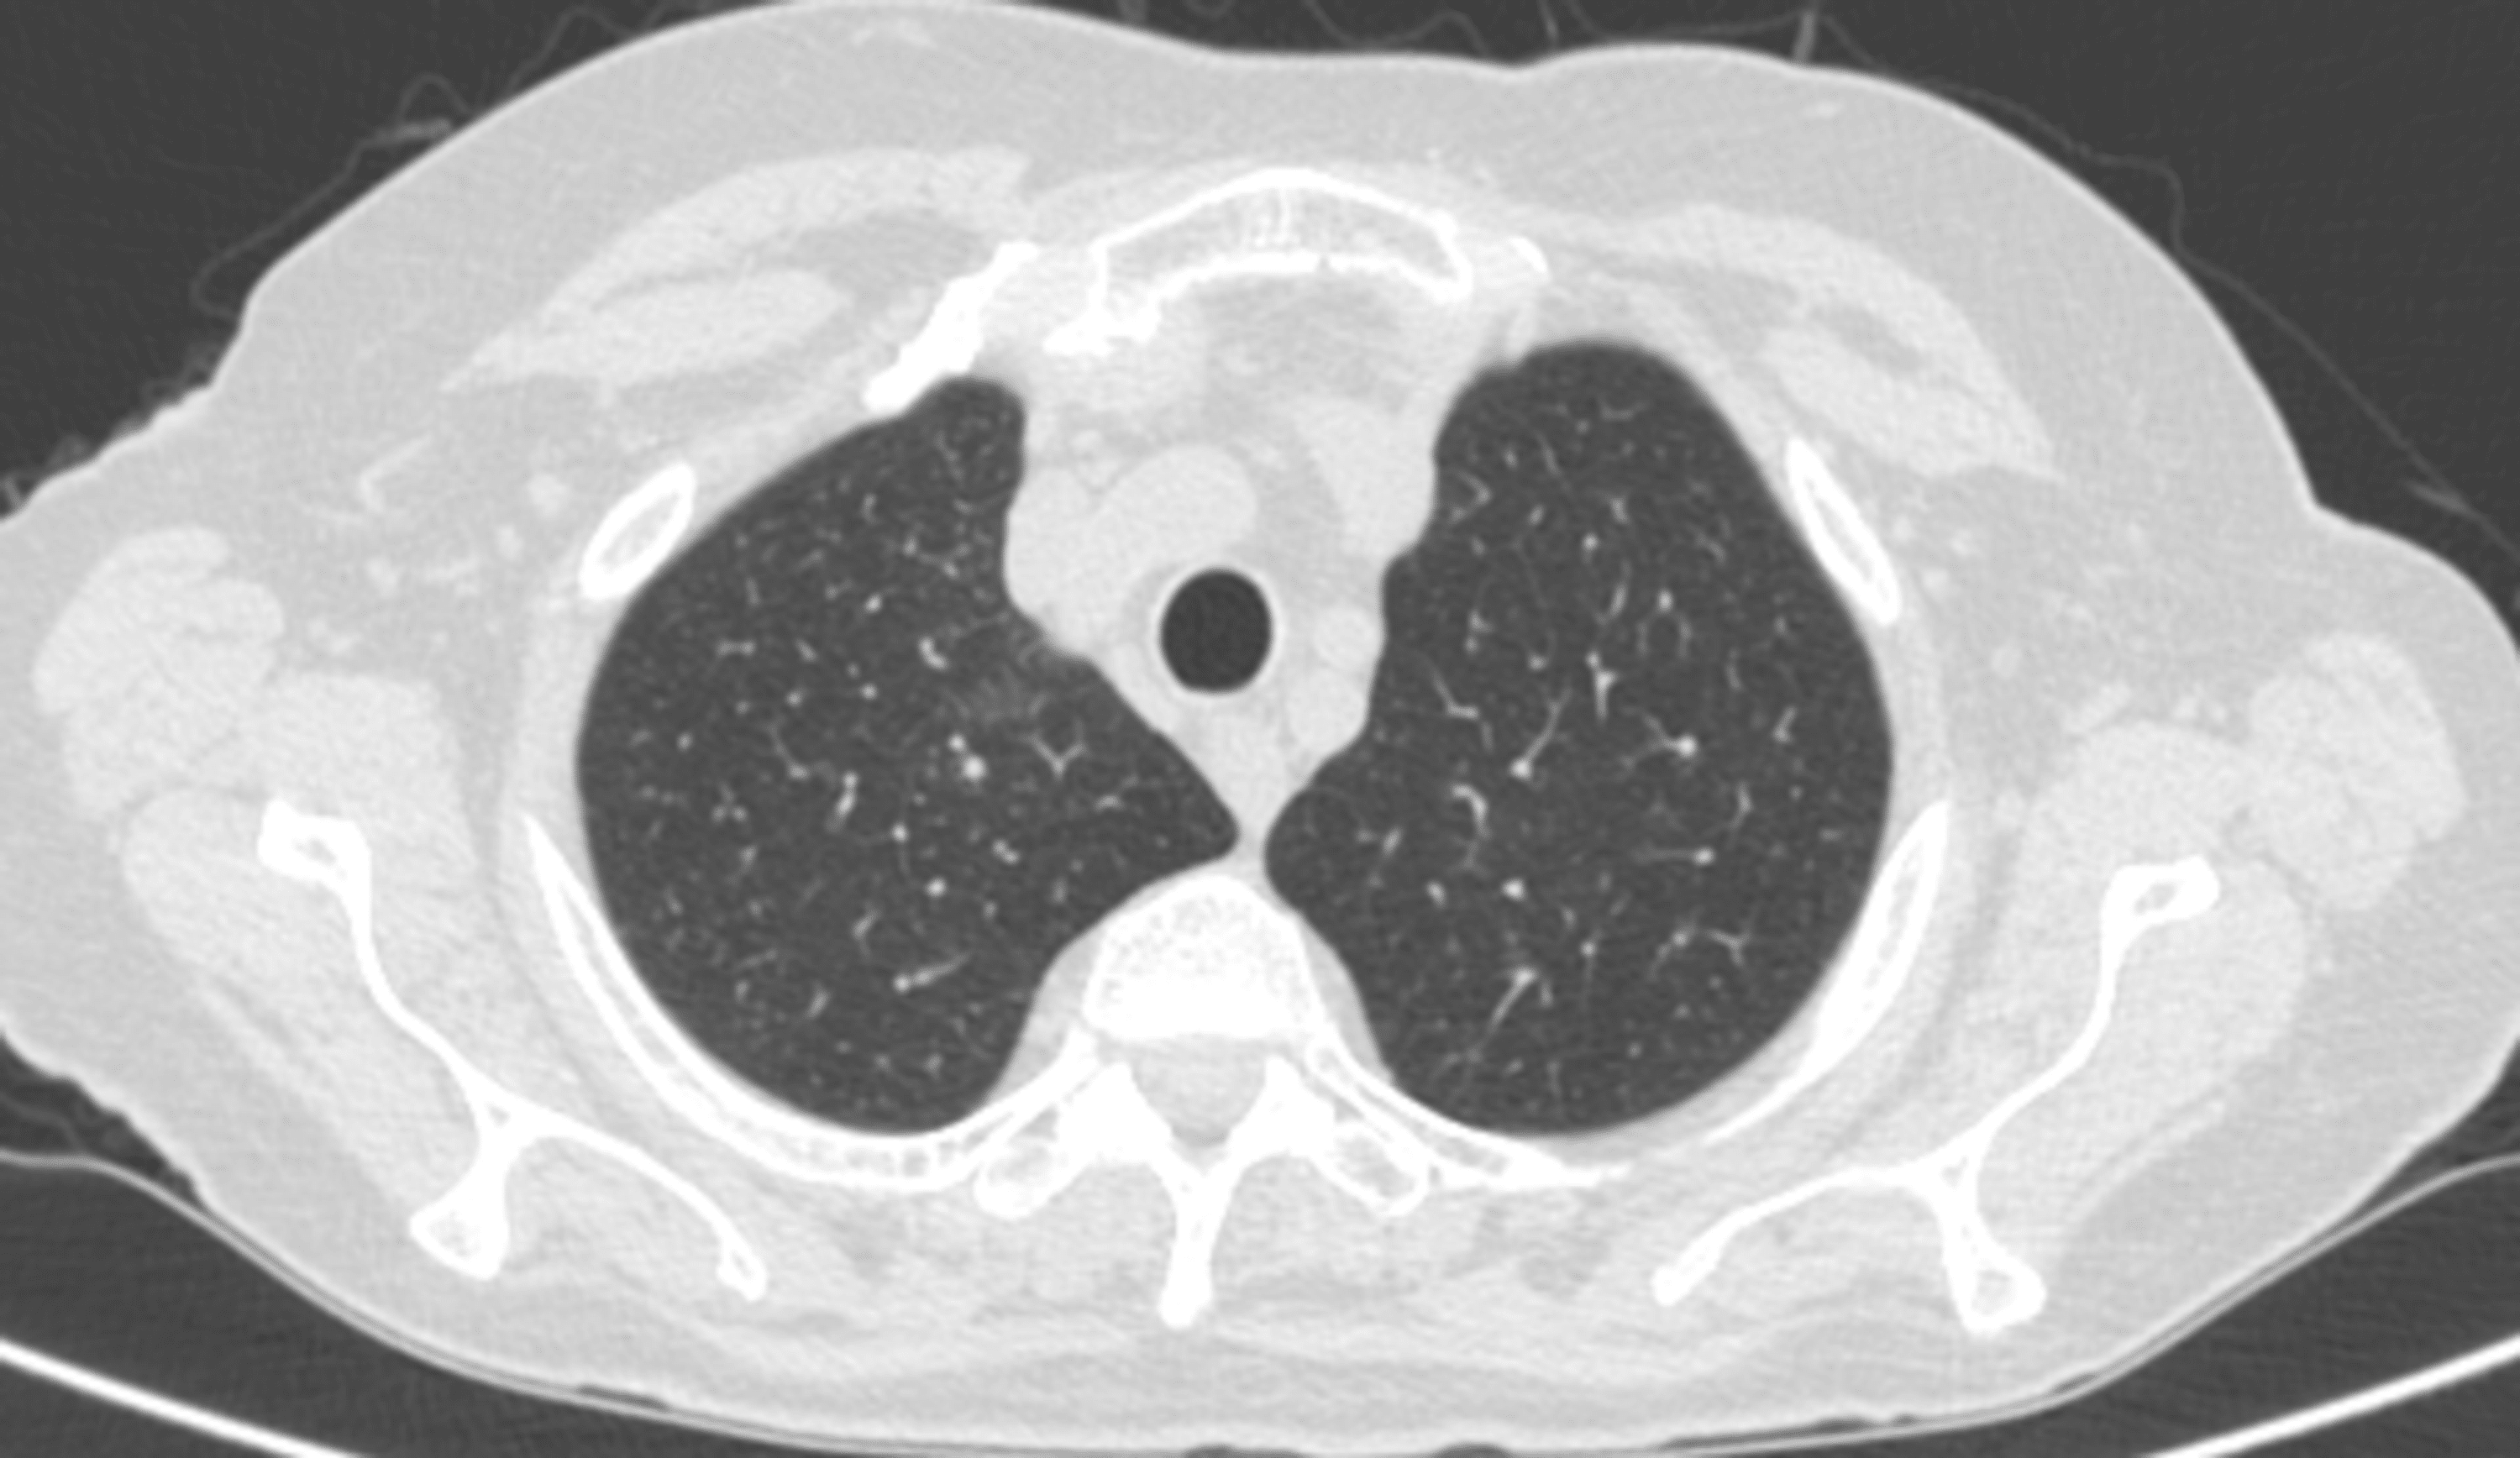

From www.cureus.com

Cureus Sinusitis and LateOnset Asthma A Red Flag of Eosinophilic Red Flags For Sinusitis This article examines the symptoms, signs, presentation, investigation, and management of nasal and sinus neoplasia, and details the ‘red. Sinusitis (also known as rhinosinusitis) is a symptomatic inflammation of the mucosal lining of the paranasal sinuses and nasal cavity. They are caused by mucosal inflammation, which inhibits mucociliary. For those with signs of acute bacterial rhinosinusitis (e.g. Acute and chronic. Red Flags For Sinusitis.

Sinusitis and LateOnset Asthma A Red Flag of Eosinophilic Red Flags For Sinusitis Acute and chronic sinusitis are common primary care presentations. They are caused by mucosal inflammation, which inhibits mucociliary. Subtypes of rhinosinusitis include acute, subacute, recurrent acute, and chronic. Rhinosinusitis is one of the most common conditions for which patients seek medical care. This article examines the symptoms, signs, presentation, investigation, and management of nasal and sinus neoplasia, and details the. Red Flags For Sinusitis.

From www.researchgate.net

(PDF) Sinusitis and LateOnset Asthma A Red Flag of Eosinophilic Red Flags For Sinusitis They are caused by mucosal inflammation, which inhibits mucociliary. Sinusitis (also known as rhinosinusitis) is a symptomatic inflammation of the mucosal lining of the paranasal sinuses and nasal cavity. For those with signs of acute bacterial rhinosinusitis (e.g. Rhinosinusitis is one of the most common conditions for which patients seek medical care. Acute and chronic sinusitis are common primary care. Red Flags For Sinusitis.

Sinusitis and LateOnset Asthma A Red Flag of Eosinophilic Red Flags For Sinusitis Subtypes of rhinosinusitis include acute, subacute, recurrent acute, and chronic. For those with signs of acute bacterial rhinosinusitis (e.g. Acute and chronic sinusitis are common primary care presentations. Acute sinusitis (also commonly known as acute rhinosinusitis) is a symptomatic inflammation of the mucosal lining of the nasal cavity and paranasal sinuses, presenting. Sinusitis (also known as rhinosinusitis) is a symptomatic. Red Flags For Sinusitis.